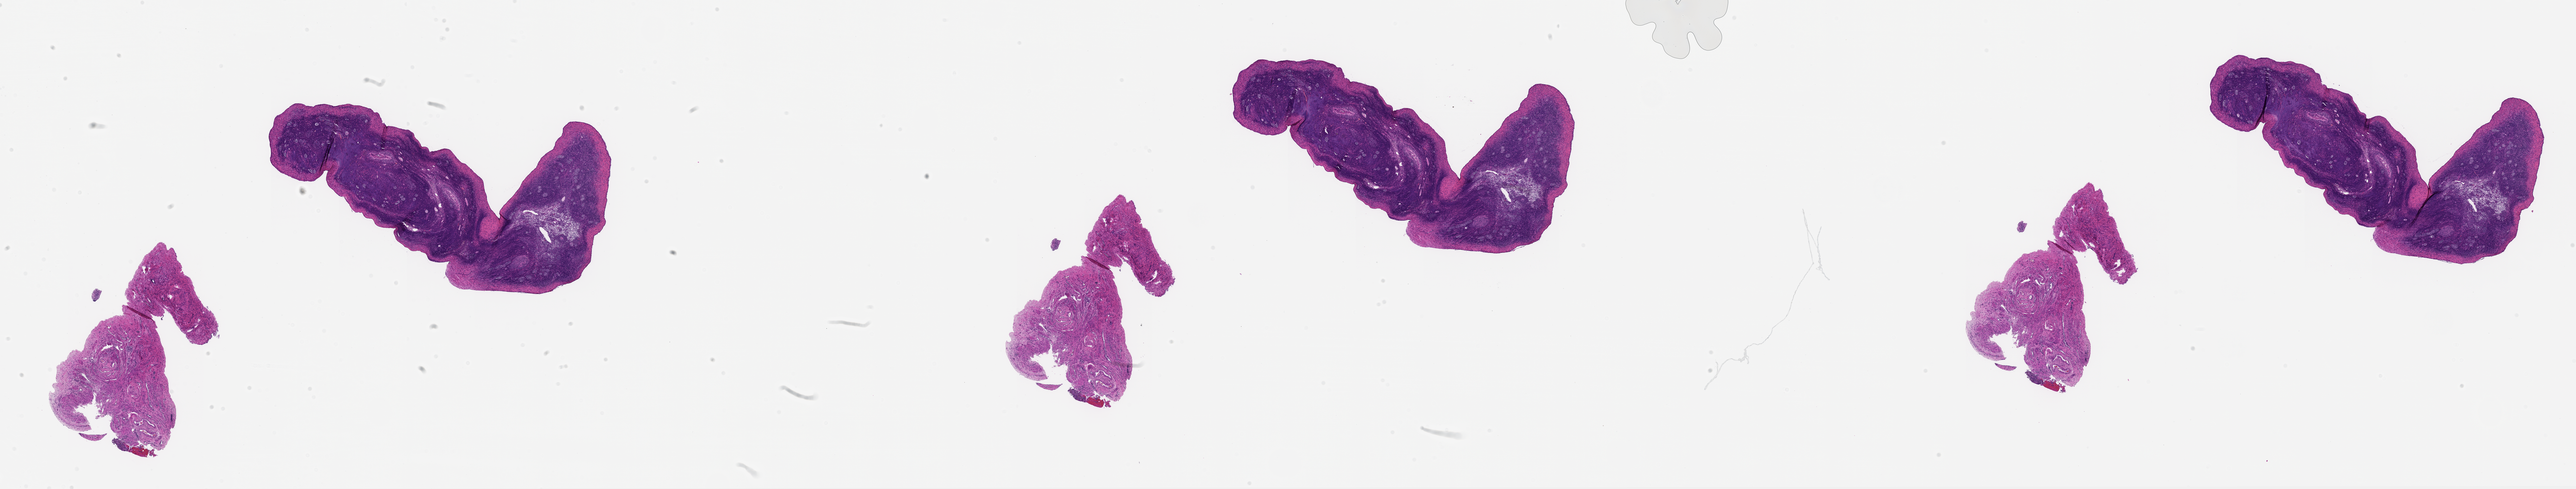

MDB0000493-38751_L_Ov_Baboon_20_yr_10_MZ_20128.tif2025-10-01 21:26 3.3G

MDB0000493-38751_L_Ov_Baboon_20_yr_10_MZ_20128_thumbnail.png2025-10-01 20:48 1.8M